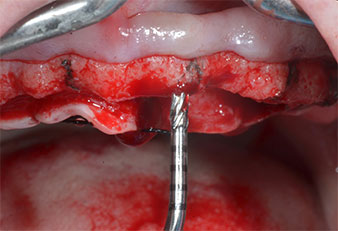

A flame-shaped, diamond-coated piezoelectric instrument (Piezomed I1) was used to mark the implant positions and to perform pilot preparation (Fig. 3). Care was taken to use an up and down movement, with reduced power, full irrigation and low pressure (below 300 g). Next a pilot instrument (Piezomed I2A/I2P) was applied for the initial 2 mm diameter enlargement of the implant sites (Fig. 4), followed by a 3 mm insert (Fig. 5).

In the present case the Z25P and Z35P instruments were not used due to the relatively soft posterior bone, which was easily managed with the I3A/I3P.

Due to the relatively hard bone (D2) in this area, the 10 mm long implant sites at positions 11 and 21 were finalized with a 4 mm diameter rotary drill, in combination with a W&H WS-75 L surgical contra-angle handpiece, the W&H Implantmed implant motor and the optional W&H Osstell ISQ module. In contrast, due to the soft bone the posterior sites were prepared to a final 3 mm diameter using the Piezomed I3P instrument. The implants were finally placed transgingivally to osseointegrate for three months (Figs. 6-10). The existing denture was retained on four provisional implants (Fig. 8).